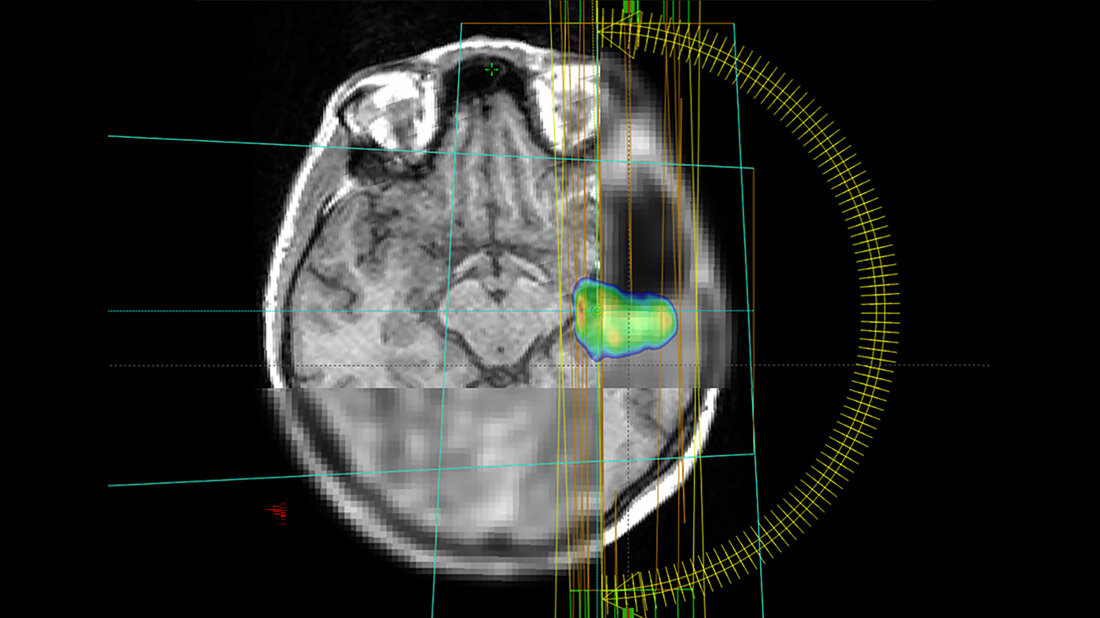

Glioblastome sind seltene, aber besonders aggressive Hirntumore. Laut Deutscher Hirntumorhilfe gibt es etwa 4.800 Neuerkrankungen p.a. in Deutschland. Mit dem Alter steigt die Erkrankungshäufigkeit. Oft werden sie mit einer Strahlentherapie behandelt. Ein internationales Forschungsteam unter Leitung des Universitätsklinikums Freiburg untersucht nun in der Studie MATTO-GBM, wie der Tumor mit maximaler Intensität bestrahlt und umliegendes, gesundes Gewebe geschont werden kann. Dabei setzen die Forscherinnen und Forscher auf eine erweiterte Bildgebung und eine Unterstützung durch künstliche Intelligenz bei der Bildanalyse. Das Projekt wird von der Europäischen Union im Rahmen des Horizon 2020-Programms über drei Jahre mit 1,2 Millionen Euro gefördert.

Statt wie bisher meist nur Bilder aus dem Magnet-Resonanz-Tomografen (MRT) zu verwenden, nutzt das Forschungsteam aus Spanien, Deutschland und Österreich in der aktuellen Studie auch die Positronen-Emissions-Tomografie (PET)-Bildgebung. „Wir wollen durch die Kombination aus MRT und PET die biologischen Eigenschaften der Tumore besser verstehen. Damit wird der Stoffwechsel im Tumor sichtbar und eine hochwirksame Bestrahlung besonders gefährlicher Tumoranteile möglich“, sagt die Physikerin Monserrat Carles Fariña, die sowohl in Valencia, Spanien, als auch am Universitätsklinikum Freiburg im Projekt aktiv involviert ist.